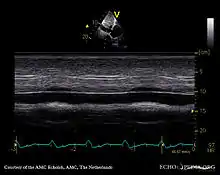

Echocardiography

If pulmonary hypertension is suspected based on the above assessments, echocardiography is performed as the next step.[12][15][56] A meta-analysis of Doppler echocardiography for predicting the results of right heart catheterization reported a sensitivity and specificity of 88% and 56%, respectively.[58] Thus, Doppler echocardiography can suggest the presence of pulmonary hypertension, but right heart catheterization (described below) remains the gold standard for diagnosis of PAH.[12][15] Echocardiography can also help to detect congenital heart disease as a cause of pulmonary hypertension.[12]

- 4-month-old with pulmonary hypertension as seen on ultrasound[59]

4-month-old with pulmonary hypertension as seen on ultrasound[59]- Long standing pulmonary hypertension[60]